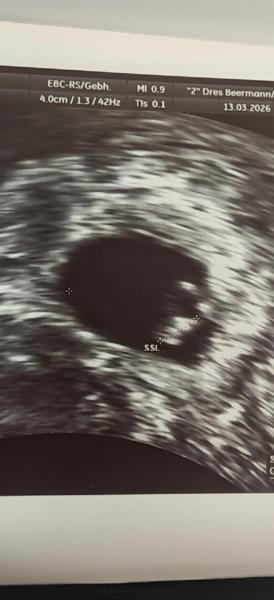

😍 hallo ihr lieben ich hatte heute meinen ersten Ultraschall bei 6 + 1 ich war so aufgeregt weil ich leider fünf Fehlgeburten hintereinander hatte umso schöner war es als ich das kleine mit einem Herzschlag sehen konnte habe geweint vor Freude mein E.t ist der 5.11 ist hier noch jemand dabei der schon seinen ersten Ultraschall hatte

Bild zu Erster Ultraschall 6+1 - Forum für November - Mamis